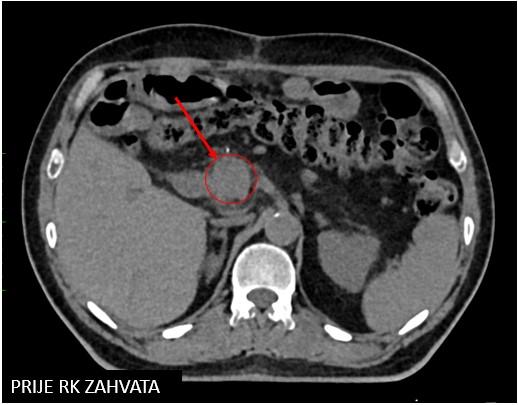

Gušterača

Bolesnica, rođena 1964. Dijagnoza: Npl renis lateris sinistri